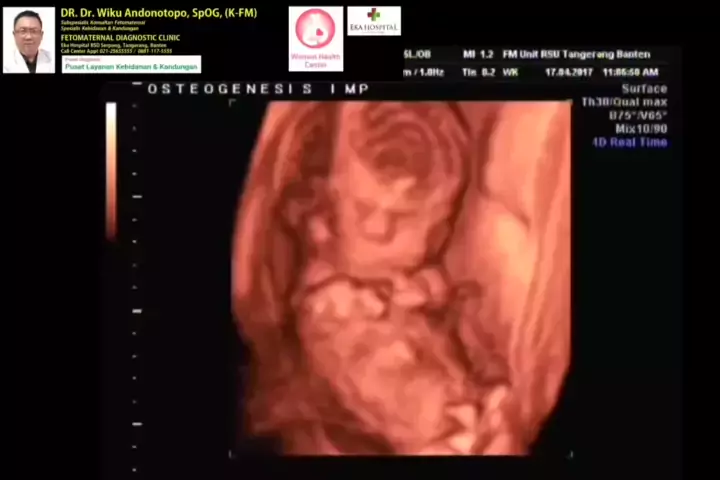

Osteogenesis Imperfecta... #osteogenesisperfecta #osteogenesisinperfecta #ekahospitalbsd #spog #fetomaternal #fetomaternal #spog #drwikuandonotopo #polikandunganekahospitalbsd #usgfetomaternaltangerang #konsultanfetomaternalbsd #kehamilansehat #fetomaternalpontianak #fetomaternalekahospitalbsd #konsultanfetomaternal #usgfetomaternalekahospitalbsd # #